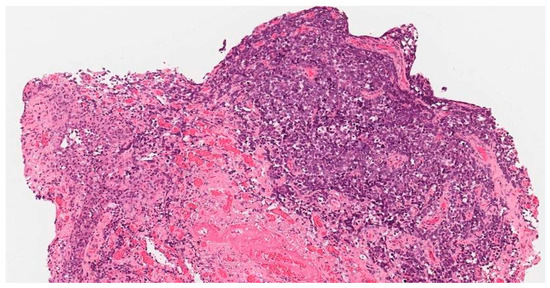

2. Case Report